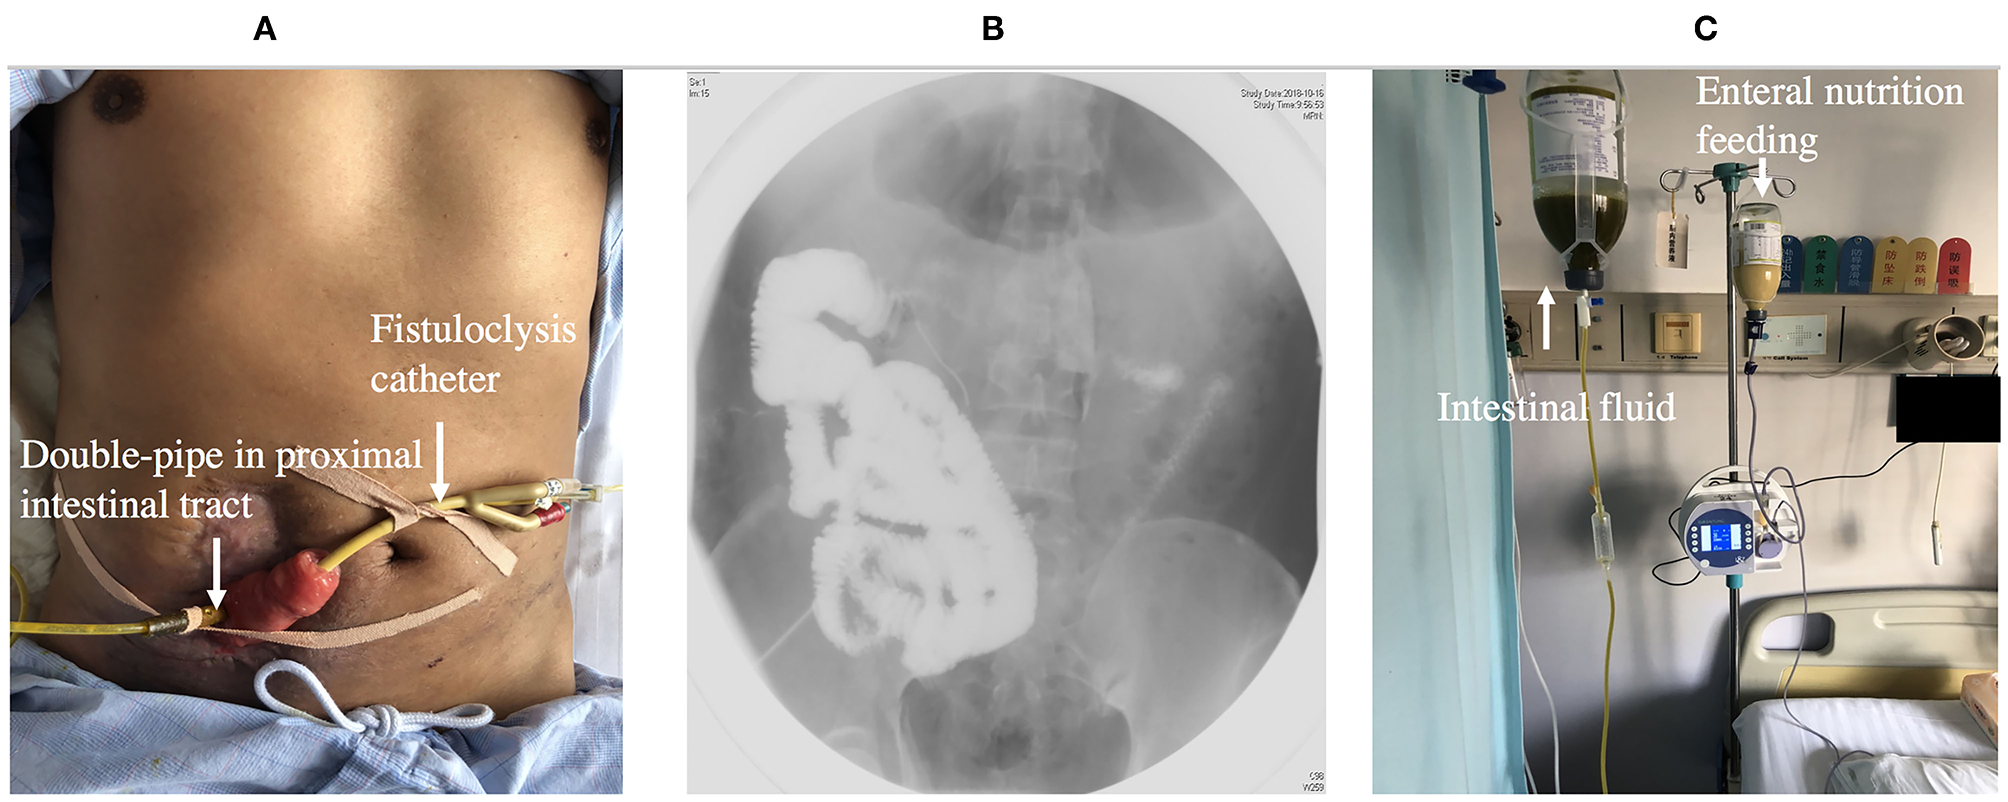

Fistuloclysis

Fistuloclysis is an option that can provide nutritional support for those fistulas that cannot close spontaneously (56, 57). After completing the investigation of intestinal integrity and length of the small intestine beyond the distal fistula, a balloon Foley catheter was intubated into the fistula. Under radiological control, the catheter was pushed to a depth of 5 cm in the distal intestinal lumen and 5 ml of water was placed in the balloon of the catheter. The proximal intestine lumen was intubated with a double-pipe to collect intestinal fluid (Figure 6). Fistulolysis has proven to be a cost-effective alternative to TPN and can also stimulate the gut mucosa. The use of polymeric feed and elemental feed can provide the effective nutritional support for ECF patients (58).

Figure 6. (A) Showing fistuloclysis: a double-pipe was intubated to collect intestinal fluid and a catheter was advanced to the lumen of the distal intestine for distal feeding. (B) Showing fistulogram before the start of fistuloclysis. (C) Showing that collected intestinal fluid was infused into distal intestinal lumen.